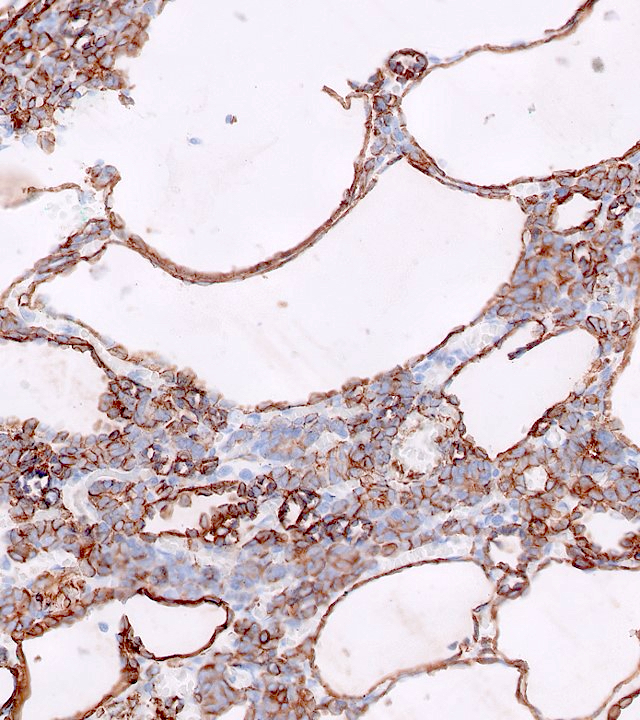

Microscopic (histologic) description

- Cysts lined with flat / cuboidal / hobnail cells (or are denuded)

- Epithelial elements consist mainly of mature and immature / abortive tubules and small papillae resembling immature glomeruli

- Key histological findings of the variably cellular septa include

- Nephroblastomatous epithelial elements

- Islands of undifferentiated blastema and differentiated mesenchymal elements (skeletal muscle and less often cartilage and fat) (J Urol 2010;183:1585)

- Focally, the septal elements may protrude into the cystic spaces in microscopic papillary folds

Microscopic (histologic) images

Contributed by Americo Brilhante, M.D. and Daniel Athanazio, M.D., Ph.D.

Positive stains

- WT1: blastemal cells (J Cancer Res Ther 2022;18:209)